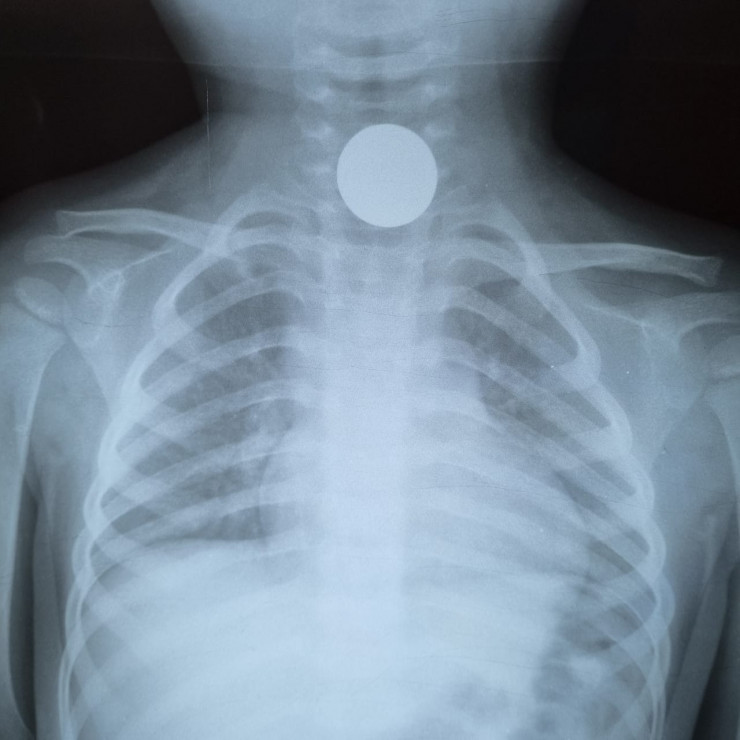

"В основном дети заглатывают инородные предметы при игре или приеме пищи. Например, монеты, плоские батарейки, бусинки, булавки, косточки от курицы и многое другое. Самое страшное в такой ситуации - затрудненность дыхания или непроходимость пищевода", - рассказывает он.

Перечень того, что вытаскивали из детских органов, огромный. Но чаще всего это монеты, камни, сережки, магниты и батарейки.

"Например, из кишечника 4-летнего малыша вытащили кольцо от связки ключей. Родители три недели не догадывались, что их ребенок проглотил его. Хотя он жаловался на боли в животе, рвоту. Потом обратились к нам. Под общим наркозом на ФГДС мы обнаружили инородное тело в 12-перстной кишке и извлекли его. Был еще случай недавно: мы вытащили из дыхательных путей 14-летнего подростка фонарик от зажигалки. Примечательно то, что юноша месяц ходил и никому не рассказывал об этом, пока при обследовании на рентгене случайно не обнаружили инородное тело в дыхательных путях", - рассказал Серик Нусипкожаев.